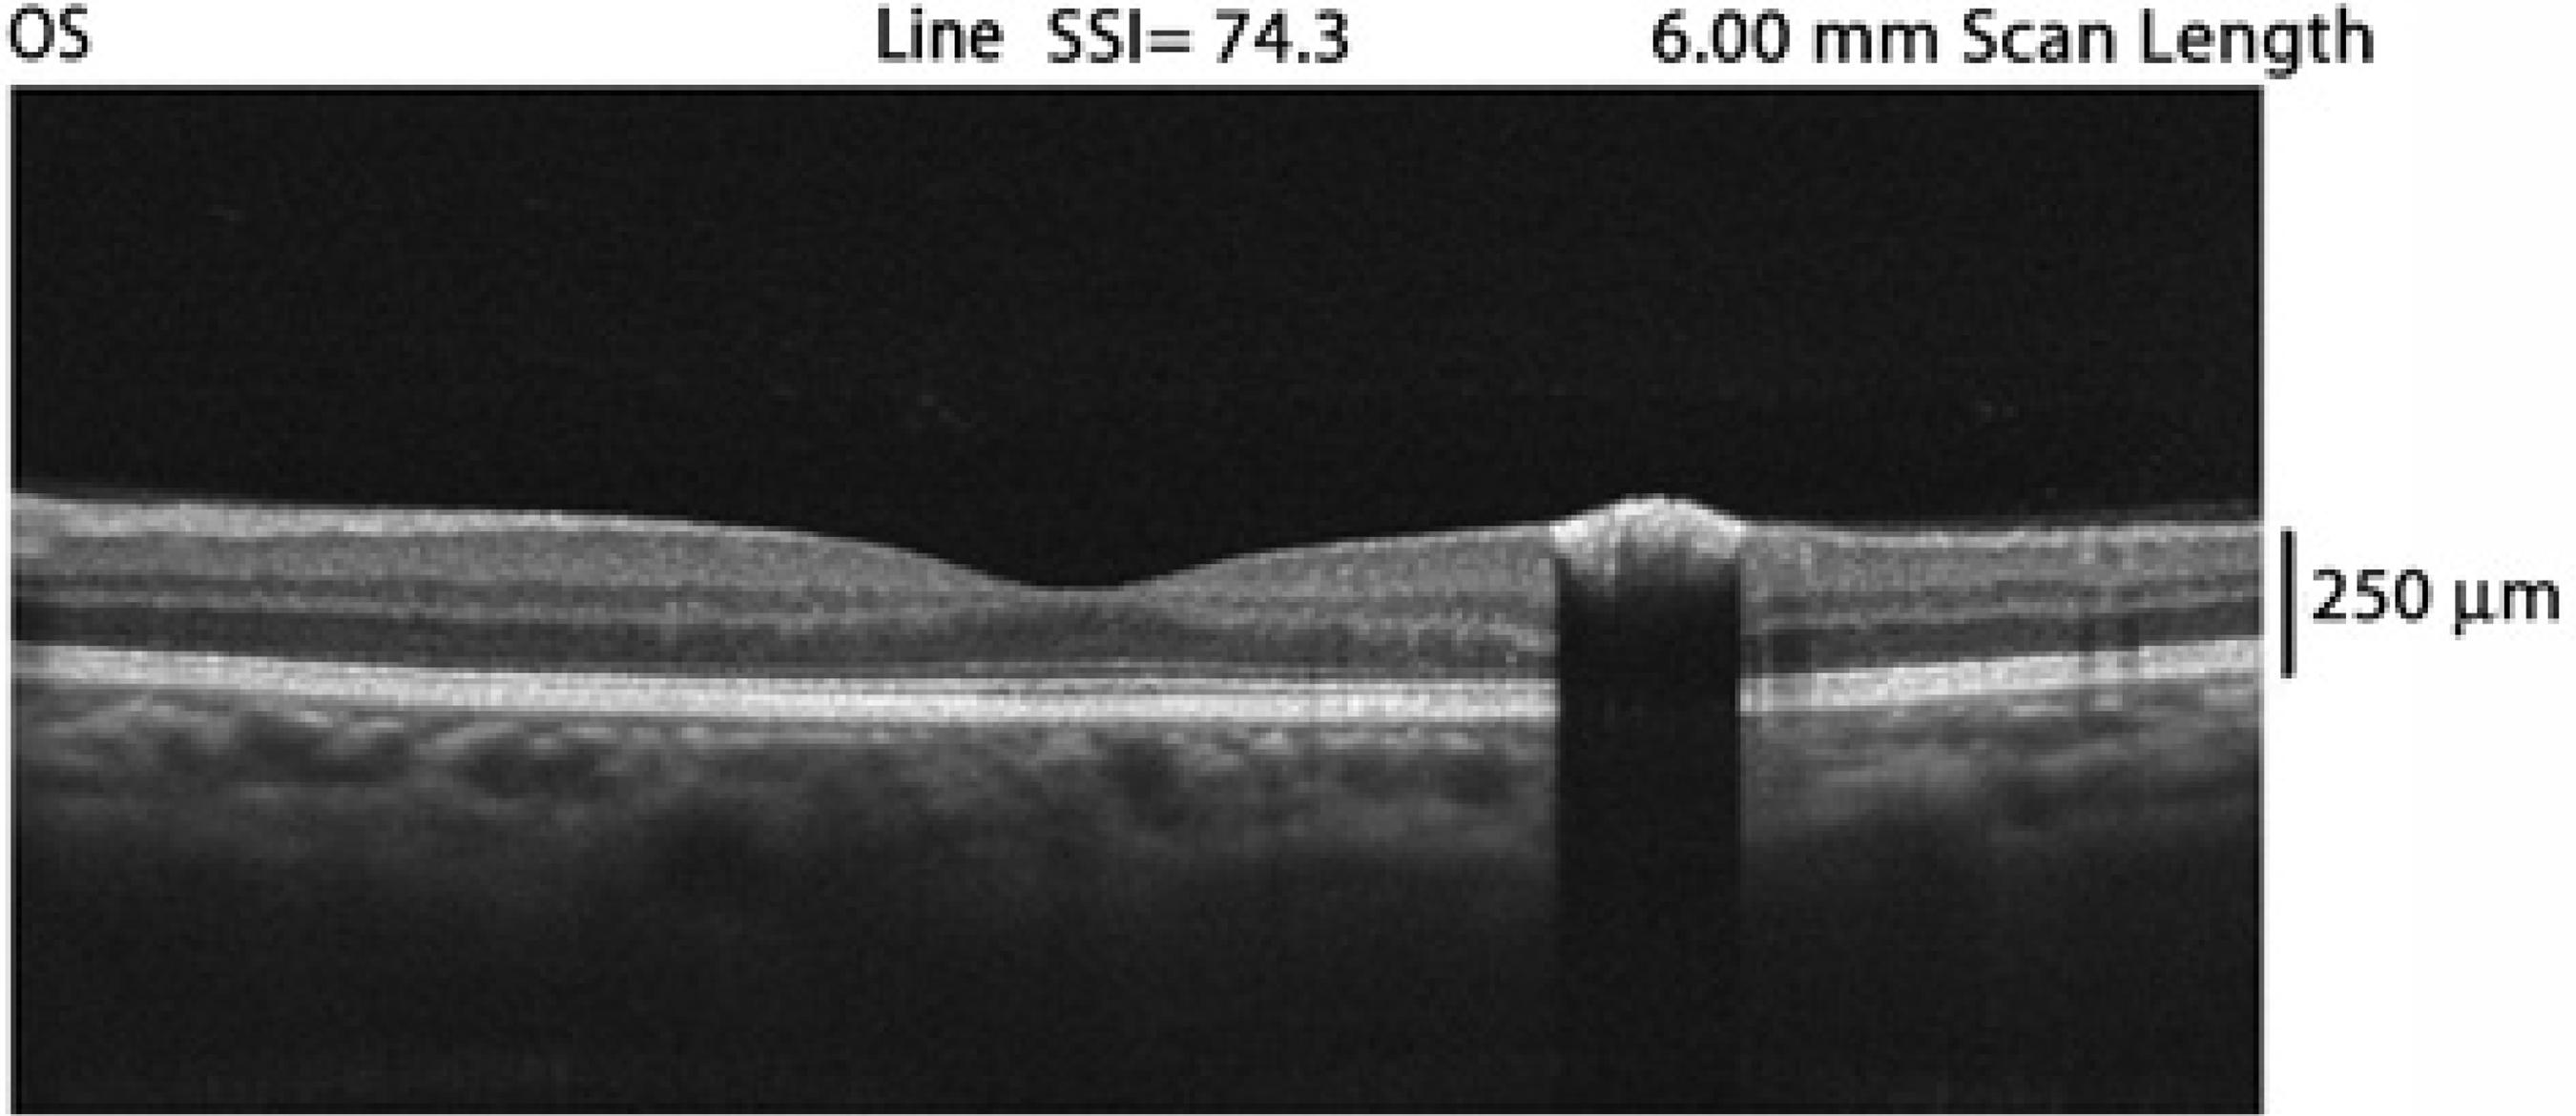

Fluorescein angiography and OCT were performed. Angiography revealed a nonfluorescent lesion during all the phases of the examination, including the late phases (Figure 1). OCT revealed an abruptly elevated hyper-reflective mass with deep optical shadowing (Figure 2). The diagnosis was compatible with CSHRPE, and the patient was followed by observation.

CSHRPE is a benign tumor that is incidentally diagnosed and involves all layers of the retina. This hamartoma is presumed to be a congenital lesion. It is a rare tumor that can be detected during routine fundus ocular examination. On clinical examination, it appears as a solitary macular lesion that is darkly pigmented, well-defined, and involves the full thickness of the retina. Although FA findings were unremarkable in the present case, hyperfluorescence is occasionally observed in the late phases(1,2). OCT typically shows a complete blockage of optical transmission.

OCT is a useful noninvasive examination that can help in diagnosis and provide information about additional features such as vitreoretinal adhesion(10).